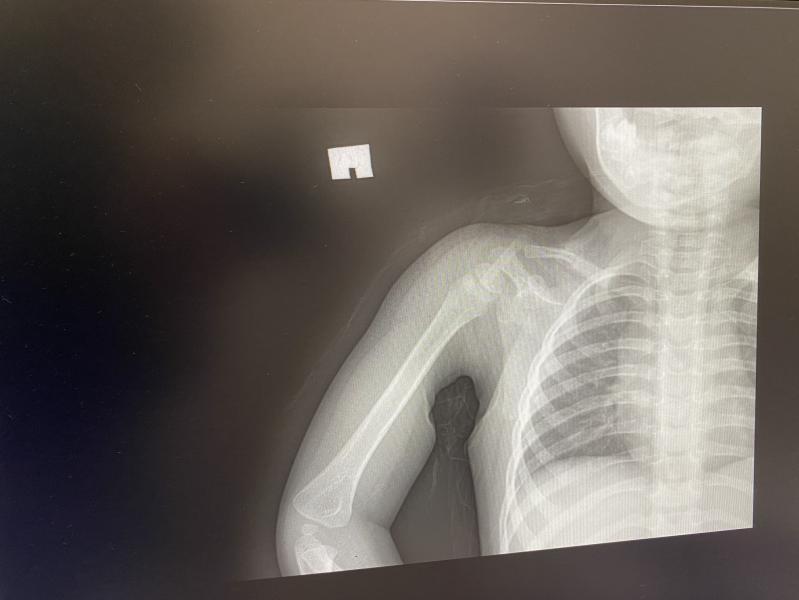

у кого дети ломали ключицу? отзовитесь🥲